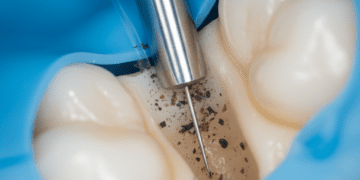

- Utilização dos instrumentos: Praticar as técnicas com os instrumentos odontológicos reais, como espelhos, pinças, brocas e curetas, desenvolvendo a coordenação manual.